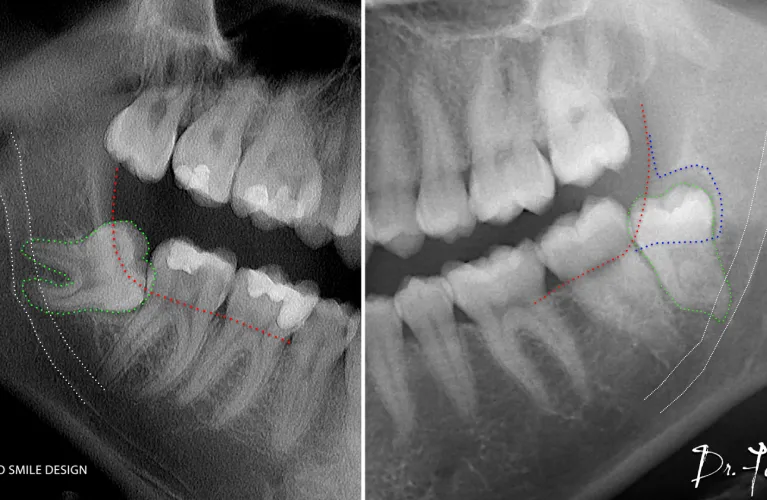

Pre-Operative Xray Required

OPG

CBCT

Wisdom teeth, or third molars, are the last set of teeth to develop, typically forming after the second molars around the ages of 17 to 19. They usually begin to emerge in the late teens or early twenties. While wisdom teeth may remain healthy and functional for some individuals, they often pose complications due to insufficient space in the dental arch, preventing normal eruption. When this happens, the wisdom teeth become “impacted,” meaning they remain trapped beneath the gumline or within the jawbone, necessitating removal to avoid further problems.